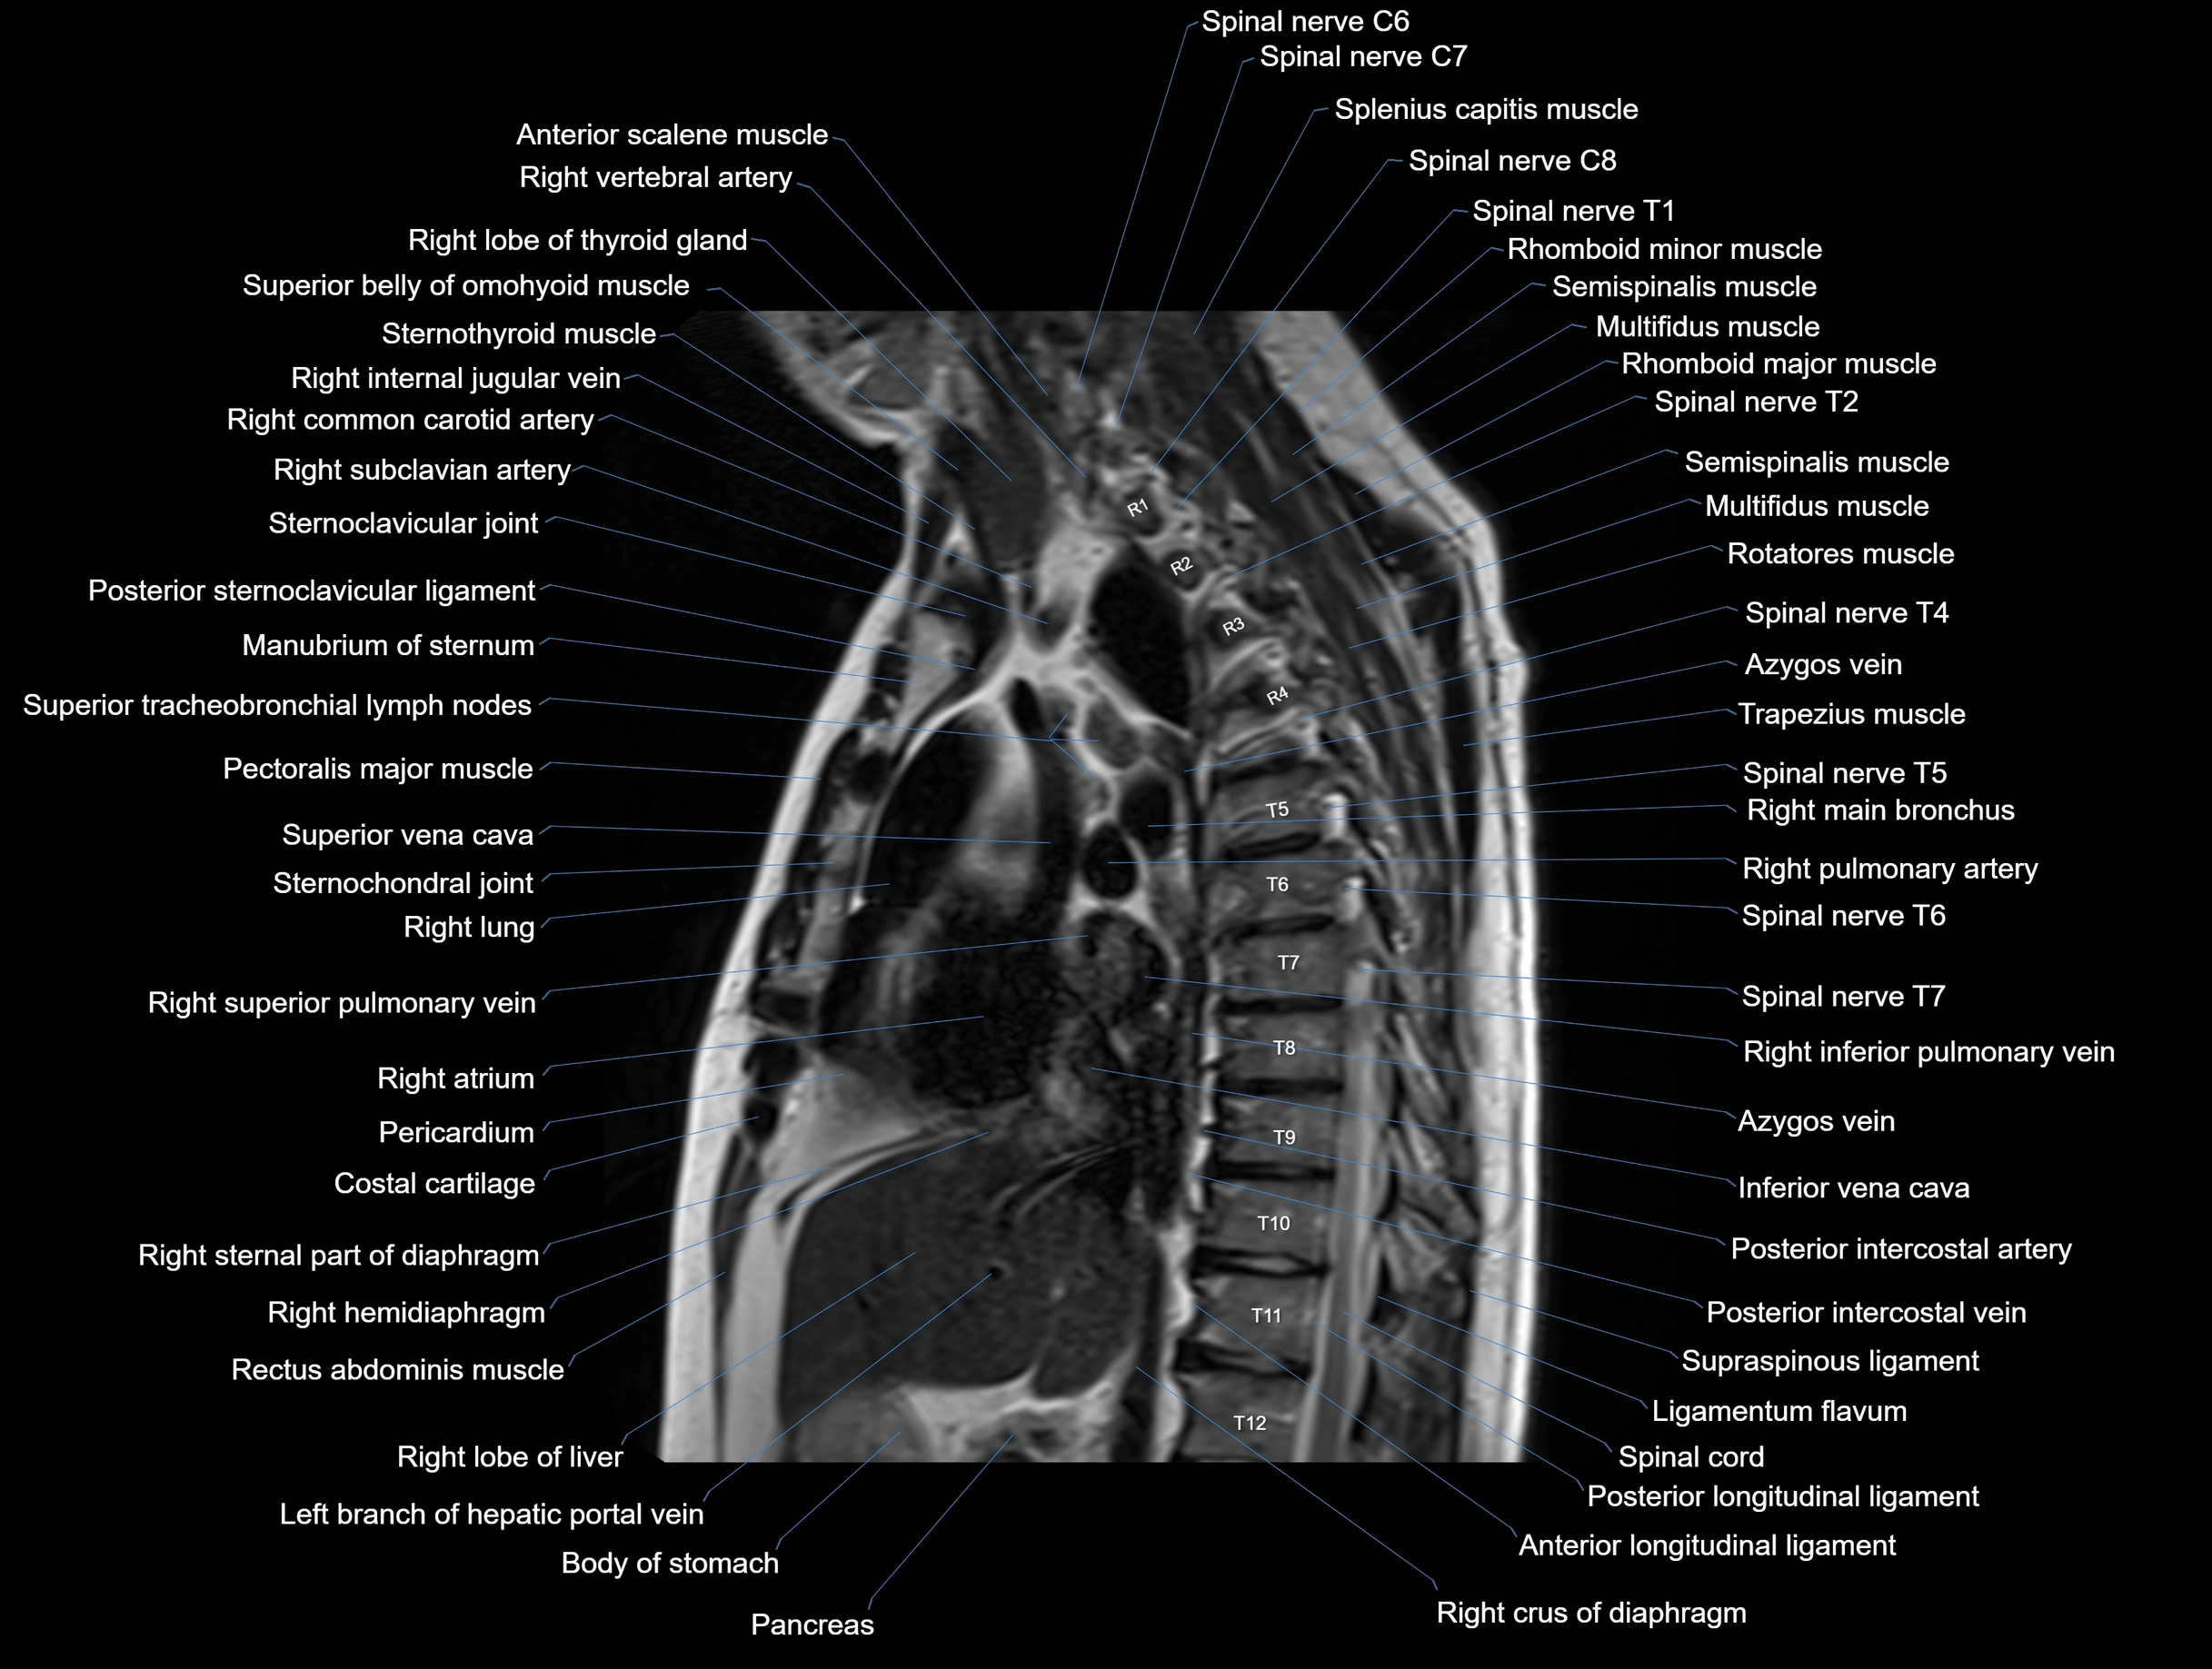

- T (Thoracic spine)